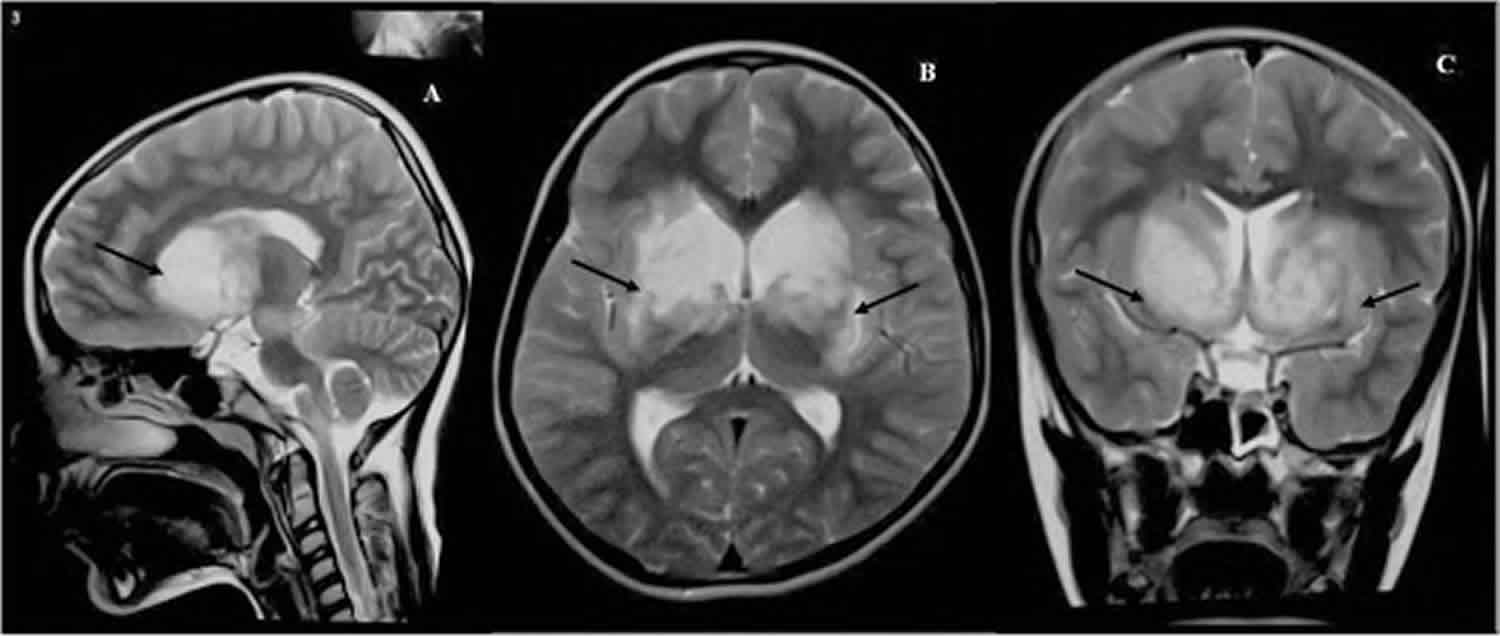

Brain imaging studies have demonstrated that people who suffer from conversion disorder have irregular blood flow to various parts of their brains.

The Alice in Wonderland Syndrome, also known as AWIS, is typically brought on by brain inflammation in young children.

Migraines are frequently the cause of the syndrome in adults. Around fifty percent of patients are able to make a full recovery with the help of treatment, the specifics of which can change depending on the underlying cause.

However, in severe situations, AWIS can be an indicator of Creutzfeldt-Jakob disease, which is a neurodegenerative condition that ultimately results in death.